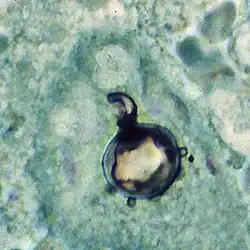

The yeast reproduces by asexual budding, where daughter cells are borne asynchronously at multiple, random positions across the cell surface. Buds begin by layers of cell wall increasing in optical density at a point that eventually gives rise to the daughter cell.[3] Once the bud has expanded, a cleavage plane develops between the nascent cell and the mother cell. Following dehiscence, the bud scar disappears.[8] In tissue, budding occurs inside the granulomatous center of the disease lesion, as visualized by hematoxylin and eosin (H&E) staining of histologic sections.[10] Nonbudding cells measure 5–15 μm in diameter, whereas those with multiple spherical buds measure from 10–20 μm in diameter.[10] In electron microscopy, cells with multiple buds have been found to have peripherally located nuclei and cytoplasm surrounding a large central vacuole.[12] In the tissue form of P. brasiliensis, yeast cells are larger with thinner walls and a narrower bud base than those of the related dimorphic fungus, Blastomyces dermatitidis.[10] The yeast-like form of P. brasiliensis contains multiple nuclei, a porous two-layered nuclear membrane, and a thick cell wall rich in fibers, whereas the mycelial phase has thinner cell walls with a thin, electron-dense outer layer.[8]

Paracoccidioides brasiliensis causes mucous membrane ulceration of the mouth and nose with spread through the lymphatic system. A hypothesized portal of entry for the fungus to the body is through the periodontal membrane.[30][31] The route of infection is assumed to be inhalation following which the infective propagule gives rise to the distinctive multipolar budding yeast forms in the lung resembling a "ship's wheel" seen in histological sections.[9][32] Both immunologically normal and compromised people are at risk for infection.[9] The lungs, lymph nodes, and mucous membrane of the mouth are the most frequently infected tissues.[10] The pathological features of paracoccidioidomycosis are similar to those seen in coccidioidomycosis and blastomycosis.[33] However, in the former, the lesions first appear in the lymphoid tissue and then extend to mucous membranes,[33] producing localized to diffusive tissue necrosis of the lymph nodes.[33] The typically extensive involvement of lymphoid tissue and the limited occurrence of the gastrointestinal tract, bone and prostate set the clinical picture of paracoccidioidomycosis apart from that of blastomycosis.[10][33]